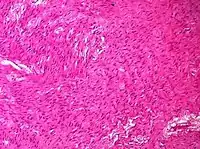

| Sex cord-stromal tumor: pure stromal tumors, pure sex cord tumors and mixed sex cord-stromal tumors | Ovarian fibroma | 1.5% | 0% | Spindle-shaped fibroblastic cells and abundant collagen.[19] | ![]() | ![]() |